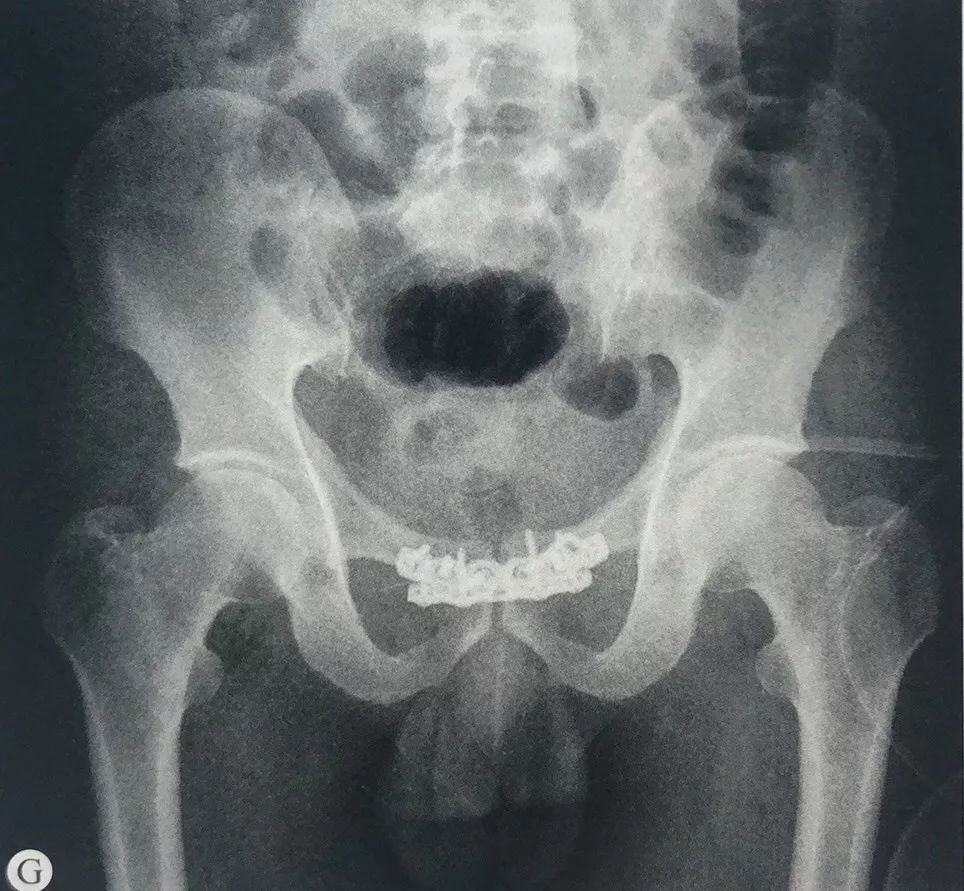

Feb 07, 骨粗鬆症による骨強度 (骨密度と骨質) の低下が原因となり, 軽微な外力 (立位姿勢からの転倒か, それ以下の外力で歩行や寝返り等も含まれる) で生じる骨盤の骨折です なお, 骨盤は左右の寛骨 (腸骨, 坐骨, 恥骨) , 後方の仙骨と尾骨からなる閉鎖環状構造を3DCTでは左の恥骨骨折も認めています。 この症例は、後方骨盤輪の離開を認めておらず日本外傷学会分類のⅠaの骨盤骨折に相当します。 症例 50歳代 男性 交通外傷疲労骨折とは、「骨折」という名前こそ付いていますが、一回の大きな外力で発生するいわゆる通常の外傷性の骨折とは異なります。むしろ小さな弱い外力が繰 り返し加わることによって軽い損傷が治ることなく残っている状態をいいます。 恥骨→長

Jul 07, 16「腸骨翼骨折」「恥骨骨折」「坐骨骨折」を 安定型 、 「腸骨骨折」「仙骨骨折」「船長関節離開」を 不安定型 に分類しています。 ※安定型はズレにくく、不安定型はずれる可能性がある。 骨盤骨折の原因は?恥骨骨融解症(Pubic osteolysis以下PO)は恥骨部の疼痛・違和感にて発生し、X線にて恥骨に骨融解像を認め、特に悪性腫瘍との鑑別が問題となる疾患である。 今回、仙骨骨折後にPOを発症し歩行障害と原因不明の膀胱直腸障害を生じた症例のリハビリテーション亀裂骨折 (ひび)の症状、原因、診断・治療方法についてご紹介します。リハビリテーション科、整形外科に関連する亀裂骨折 (ひび)の治療なら病院・クリニック検索のホスピタにお任せ下さい。亀裂骨折 (ひび)の診察ができるおすすめの病院をご紹介できるのは「いまから」機能搭載のホスピタ